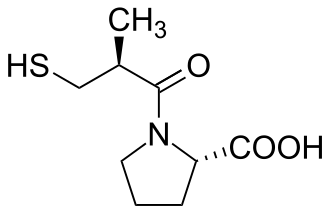

Treatment is often in the form of preventive measures of prophylaxis. Medical therapy is often prescribed to help prevent arteriosclerosis for underlying conditions, such as medications for the treatment of high cholesterol (e.g., statins, cholesterol absorption inhibitors), medications to treat high blood pressure (e.g., ACE inhibitors, angiotensin II receptor blockers),[2] and antiplatelet medications. Lifestyle changes are also advised, such as increasing exercise, stopping smoking, and moderating alcohol intake.[1]